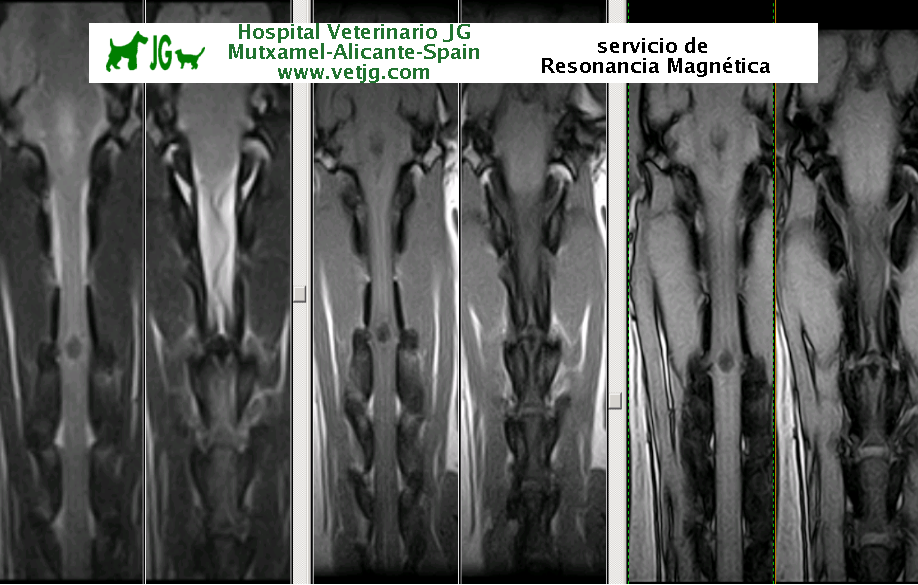

Caso 1: imágenes de resonancia magnética de un perro con síndrome cervical motivado por una hernia discal a nivel de C3-C4

Copyright 2017, Hospital Veterinario JG Mutxamel - Alicante - España